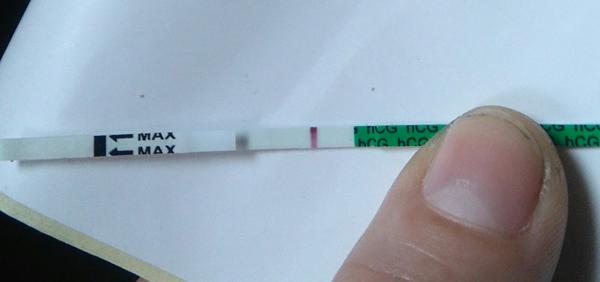

Môže ešte silnieť čiarka?

Ahojte, 8 mesiacov sa snazime o druhe dieta. Sex sme mali pred 17 dnami a 16 dnami. Vtedy som mal pravdepodobne aj ovulaciu. Dnes mam 29 den cyklu, ale zacala mi ms chodit nepravidelne. Minuly mesiac som mala po 21 dnoch, predtym zvacsa po 27-28 dnoch. Mala som pred 6 dnami mierne spinenie, co mavam zvacsa pred ms. Teraz som si robila test, su tam dve ciarky, myslite ze bude test silniet? Bojim sa aby som nedostala biochemicke, mam si davat nieco na posilnenie?

@tehulka2016 drzim palce, vyzera to super 🙂 a ono nebude uz o moc tmavsia, ono to nie je az take tmave ako kontrolna 🙂

@tehulka2016 podla mna je tam krasna druha ciarka😍to si mala vidiet toho mojho slabunkeho ducha na teste...a z toho ducha,je teraz taka velka lopta na mojom brusku😂😂😂Drzim palce

Ja som si takyto test robila v den meskajucej ms a mala.som presne takuto druhu ciarku ako mas ty...spravila som si aj nasledujuce tri dni za sebou a myslela som ze tie ciarky budu silniet,ale boli stale rovnake...ale uz sme v siesmom mesiaci klop klop...takze si myslim ze silnost/slabost ciarky nic neznamena, pisu to aj na tych testoch, a ak o to mas prist,stane sa (aj mne raz v 10tt),teraz sa ale nad tym netrap a mysli pozitivne! A blahozelam a drzim palce!!!

Mne vôbec nesilneli čiarky, boli viditeľné ale nikdy nie rovnako tuhé, preto som prvé tri týždne testovala ako šialená skoro každý deň 😂 a už som 34tt 😉 držím palce